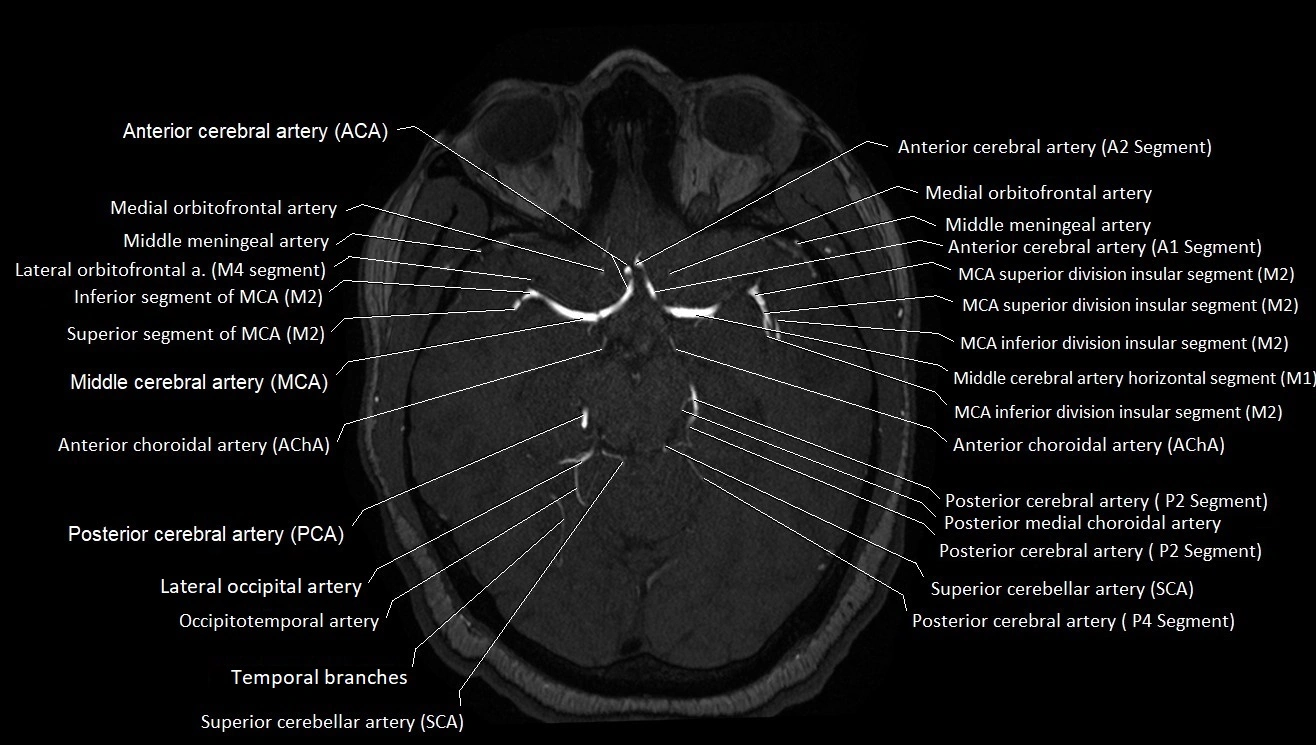

CT images

image